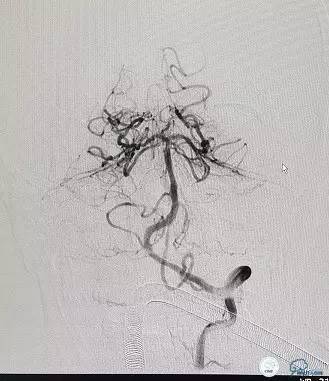

再将一枚支架(Apollo 2.75*18mm)置于闭塞段释放。造影见支架贴壁良好,左侧椎动脉颅内段狭窄处残余狭窄小于10%,左侧椎动脉远端、基底动脉、双侧大脑后动脉及其分支均显影良好,血流通畅,前向血流TICI3级(图11-13)。

图11

图12

图13